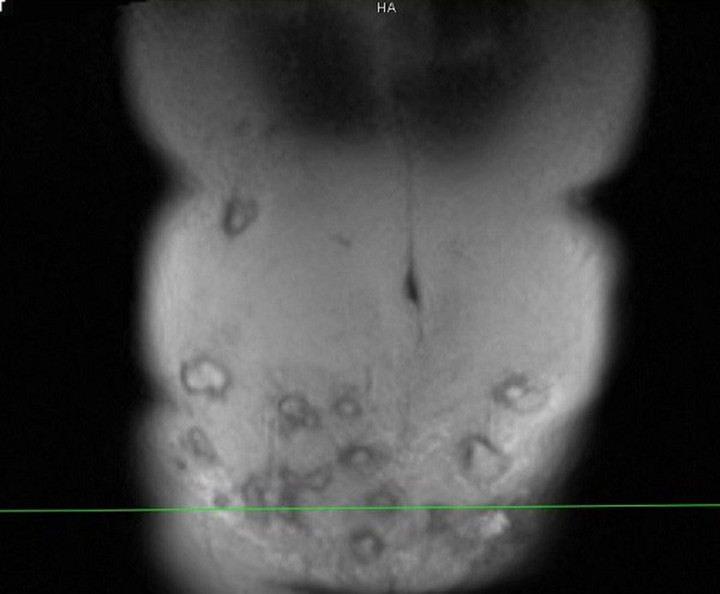

Bụng bệnh nhân có nhiều khối áp xe

Bác sĩ Minh cho biết, vùng thành bụng bệnh nhân bị viêm phản ứng nặng, vùng da ngoài thành bụng đỏ, nổi gồ ghề, sờ bên dưới có hàng chục khối tổ chức vón cục, áp xe....

“Bệnh nhân này có thể tạo hình lại thành bụng, đồng thời giải quyết được 20 khối áp xe lớn nhỏ. Tuy nhiên, do vùng tiêm rộng nên việc lấy hết ổ áp xe này không dễ dàng. Với những khối áp xe tiêm ở vị trí cao như hạ sườn thì quá trình xử lý sẽ để lại sẹo, gây mất thẩm mỹ”, bác sĩ Minh chia sẻ.